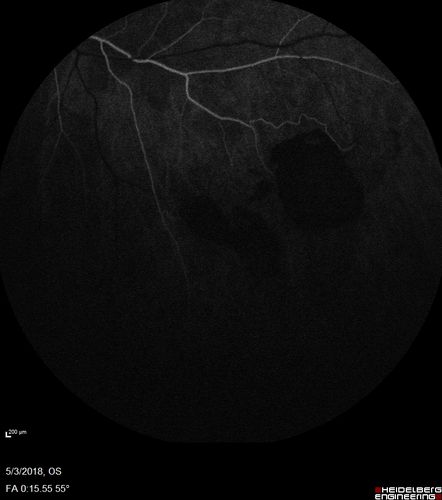

Coats' Disease -51 year old asymptomatic male

20/20 vision - had laser to non-perfusion because of proliferation.